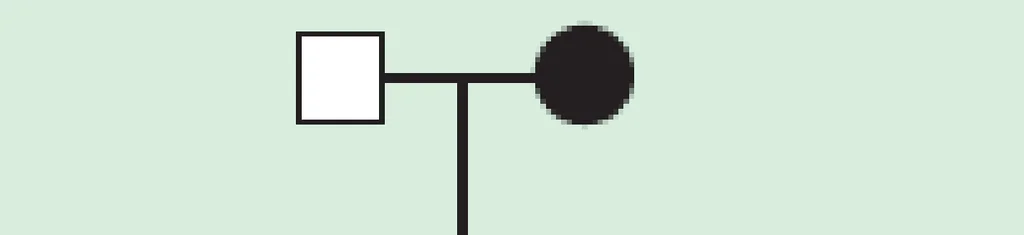

【109-1 醫學(四) 第31題】下列家族譜系最有可能為何種遺傳模式?

詳解

破題關鍵

這張家族譜系圖的解題核心在於觀察疾病的傳遞方向:只有母親會將疾病傳給所有子女,而父親不會傳給任何子女。圖片中,第一代受影響的母親將疾病傳給了所有第二代子女,而第二代受影響的男性卻沒有將疾病傳給第三代子女,這就是粒線體遺傳的典型特徵。

選項拆解